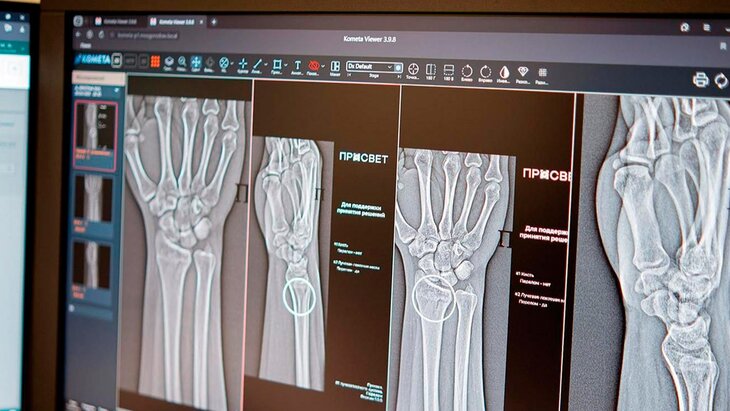

Фото: портал мэра и правительства Москвы

В Москве искусственный интеллект (ИИ) применяется в 43 клинических направлениях, включая два новых ИИ-сервиса для высокоточной диагностики множественных переломов голеностопного и лучезапястного суставов, рассказала заммэра Москвы по вопросам социального развития Анастасия Ракова.

Вице-мэр отметила, что уже более 5 лет цифровые решения помогают столичным рентгенологам, в первую очередь, в анализе медицинских снимков. Новые ИИ-сервисы способны автоматически обнаруживать на рентгеновских снимках травмы костей голеностопного и лучезапястного суставов.

"Алгоритмы автоматически отметят поврежденные участки и выполнят необходимые измерения, даже если на снимке присутствуют признаки сразу нескольких переломов. Сегодня в распоряжении московских рентгенологов уже более 60 ИИ-сервисов", – поделилась Ракова.